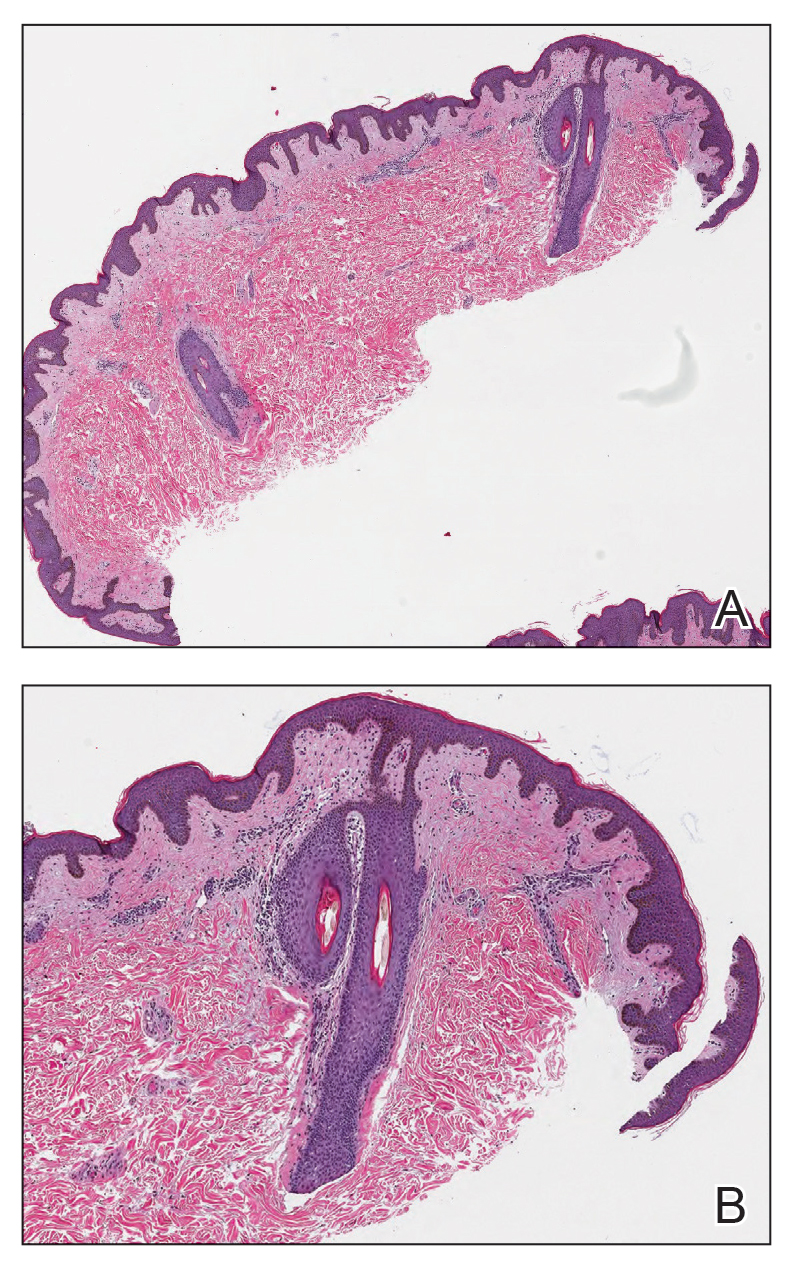

Histopathology demonstrated a lymphocyte-predominant infundibular infiltrate with mild spongiosis and lymphocytic exocytosis; a mild, superficial perivascular infiltrate also was present. The surrounding skin was largely normal with no notable papillomatosis, acanthosis, or hyperkeratosis (Figure 1). The clinical presentation and histopathologic findings led to the diagnosis of disseminate and recurrent infundibulofolliculitis (DRIF). The patient was started on a 2-week course of once-daily ammonium lactate lotion 12% and urea cream 40% and twice-daily triamcinolone ointment 0.1%. The patient was instructed to take a 1-week break before this regimen was repeated. Isotretinoin 0.5 mg/kg/d for 2 to 4 months was considered and will be an option if there is no improvement at follow-up.

The classic manifestations of DRIF, including follicular, monomorphic, flesh-colored papules distributed on the neck, trunk, and proximal upper extremities, were seen in our patient (Figure 2). These findings along with the skin biopsy identifying a lymphocytic infundibular infiltrate led to the diagnosis of DRIF. The papules associated with DRIF can be recurrent or chronic. The lesions in this patient were chronic and persistent.